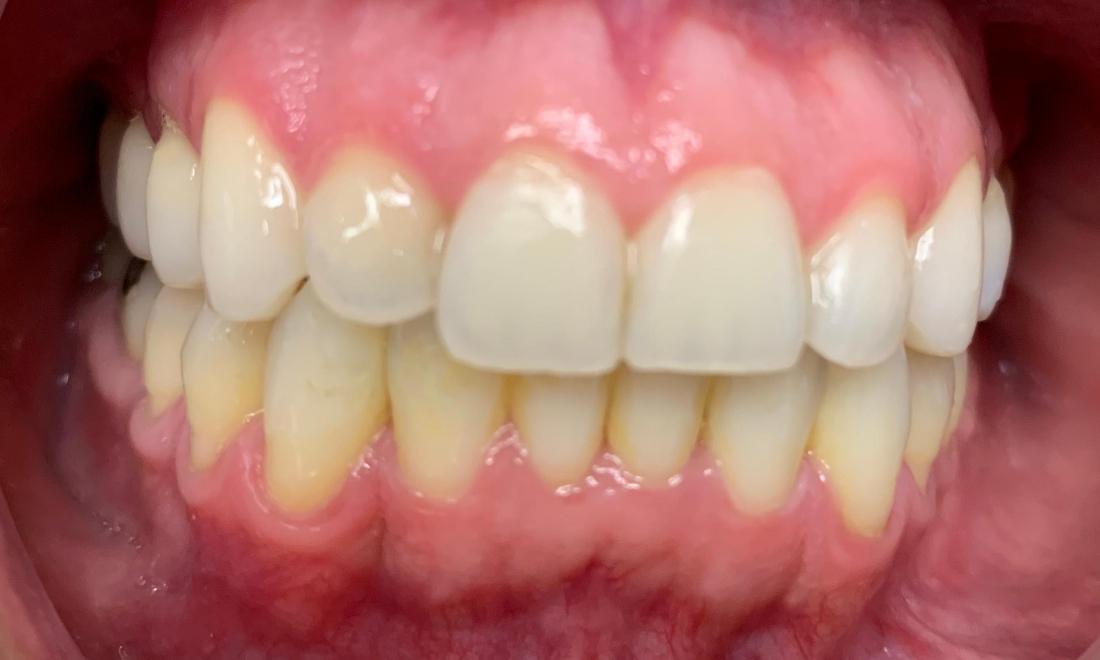

This patient's "before" photo shows their crooked, misaligned teeth and the gaps between the top and bottom rows of their smile. However, by using adult braces, we pulled their teeth into alignment and produced a straighter, healthier smile.

Clear braces allow you to achieve a straighter smile while still maintaining a sleek, professional appearance. Invisalign can help you close gaps in your smile and move teeth into proper alignment, making them easier to clean and keep cavity-free.